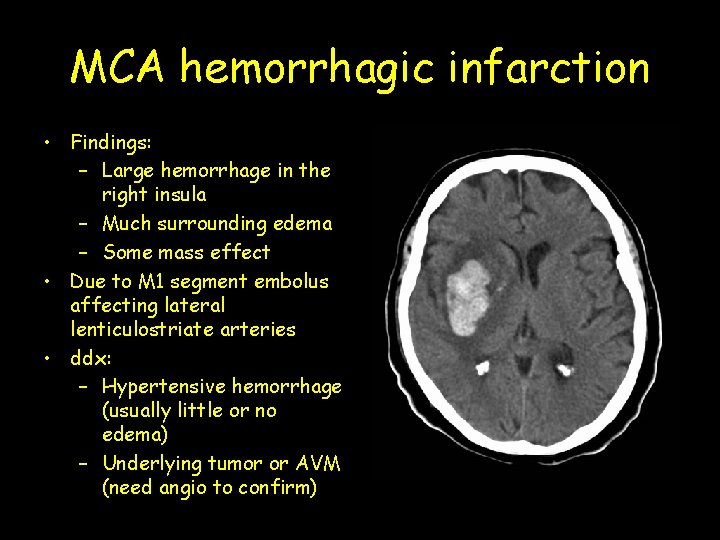

MCA hemorrhagic infarction • Findings: – Large hemorrhage in the right insula – Much surrounding edema – Some mass effect • Due to M 1 segment embolus affecting lateral lenticulostriate arteries • ddx: – Hypertensive hemorrhage (usually little or no edema) – Underlying tumor or AVM (need angio to confirm)